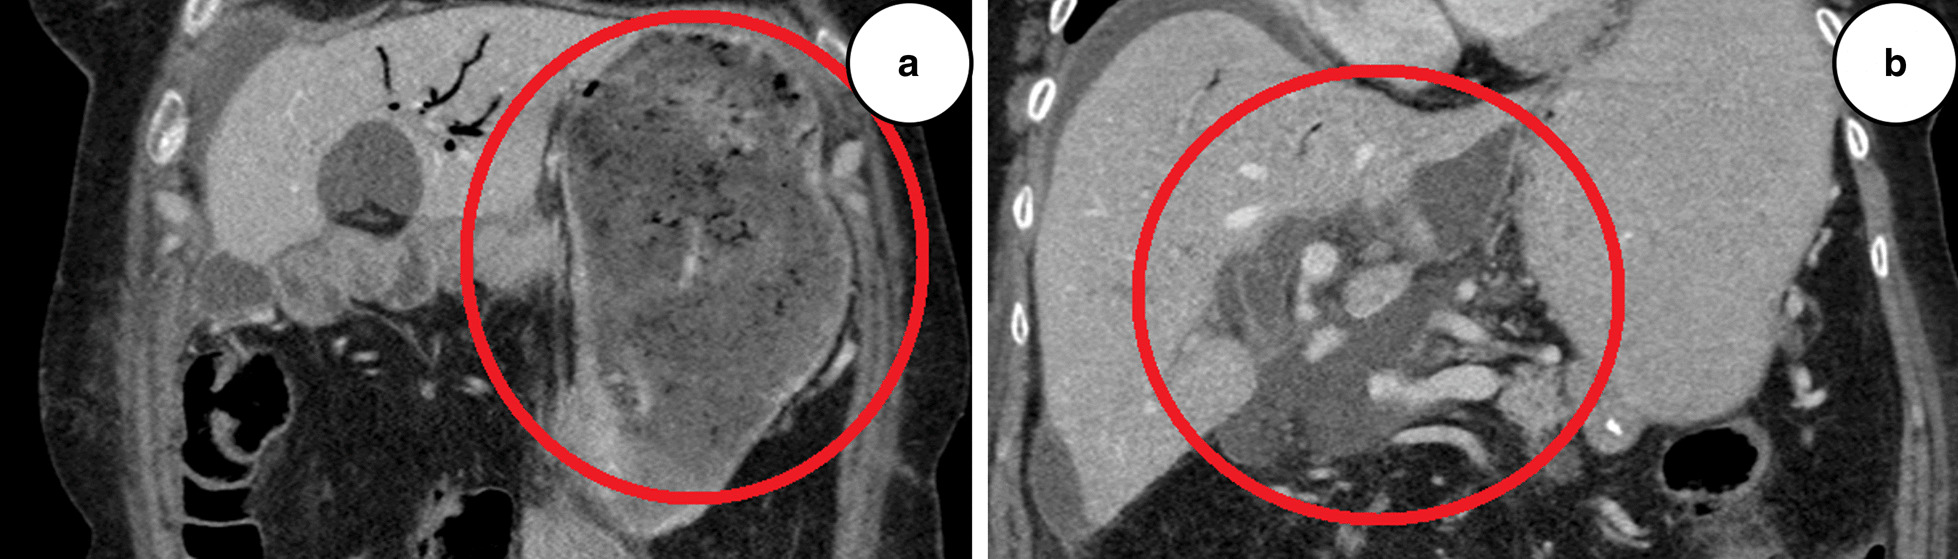

Postoperative days (POD) 1–5 were uneventful. Both drains (peak amylase levels 20 and 60 U/L) were successfully removed. On POD 7, an increased C-reactive protein (CRP) of 270 mg/L was observed. Computed tomography (CT) of the lungs and abdomen revealed peribronchial infiltrates and a small pool of free fluid in the upper right quadrant of the abdomen. The clinical condition was unremarkable, and the patient was started on intravenous antibiotics, piperacillin and tazobactam. On POD 10, a repeat CT was performed showing a large gastric retention and findings consistent with insufficient hepaticojejunostomy (Fig. 1a, b). The gastric retention was treated with a nasogastric tube, and the patient was started on parenteral nutrition. An ultrasound-guided percutaneous intraabdominal pigtail drain was established. The drain discharge was bilious to the naked eye, and the bilirubin level was 320 μmol/L. Discharge levels reached 1000 mL/day, and on POD 12 a percutaneous transhepatic cholangiography (PTC)-guided 8-French (Fr) pigtail drain was advanced through the anastomosis to deviate the leak from the abdomen.

Fig. 1.

a Computed tomography, coronal section of the upper abdomen, postoperative day 10, showing gastric retention. b Computed tomography, coronal section of the upper abdomen, postoperative day 10, showing free low-density fluid around the liver and in the vicinity of hepaticojejunostomy, consistent with insufficient hepaticojejunostomy